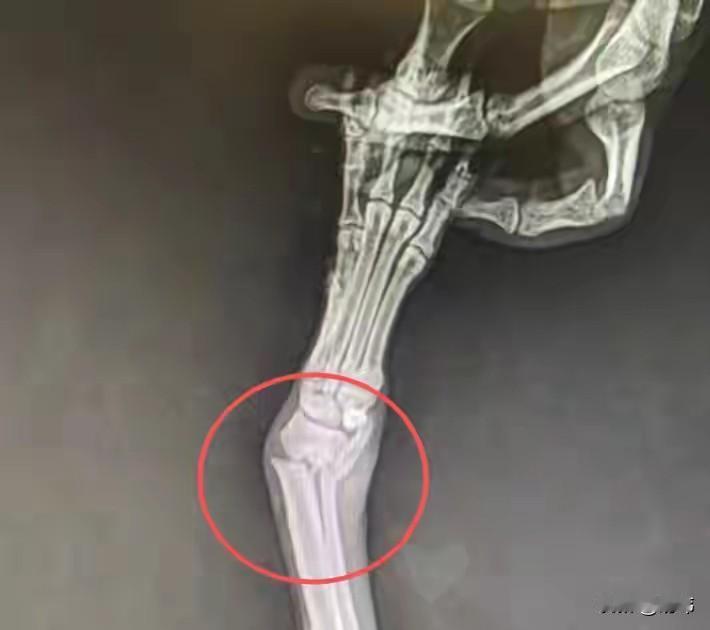

太可怜了!这天一位小姐姐和朋友去山里玩,当她们走到一个灌木丛的时候,听到有小奶狗的声音还有大狗的哀嚎,于是她们就开始找寻声音的来源。 结果她们在一个草堆里发现了六只很小的小奶狗,而在附近的水沟里看到了一只后腿受伤的狗妈妈,也不知道狗妈妈遭遇了什么,它的后腿估计是骨折了。由于它的受伤,无法走到草丛给孩子们喂奶,小奶狗们饿的痛苦的大叫。 善良的小姐姐们顿时心生怜悯,立刻把它们送去了宠物医院,经过检查,狗妈妈真的骨折了,治疗之后,还需要住院一段时间,后来它们出院后,小姐姐就收养了它们,相信在她的照顾下,狗狗一家也会越来越好的。